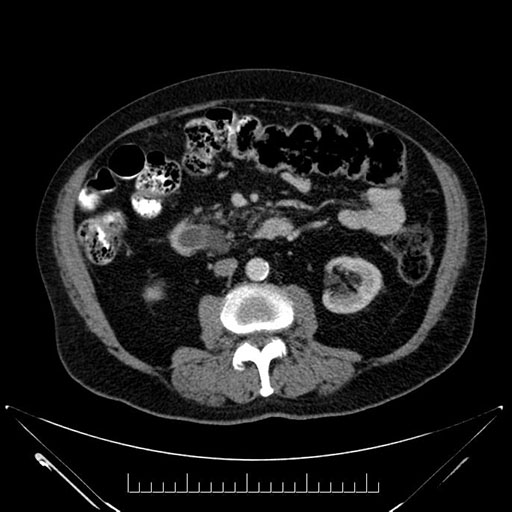

Whipple (pancreaticoduodenectomy) [case 7]

Coronal - stented